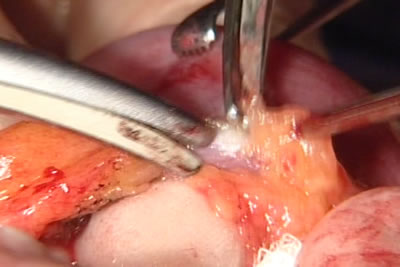

Брыжейка тонкого кишечника рассечена. Тонкий кишечник на

небольшом расстоянии освобождается от жировой ткани брыжейки.

Гемостаз сосудов брыжейки. Нужный участок тонкой кишки